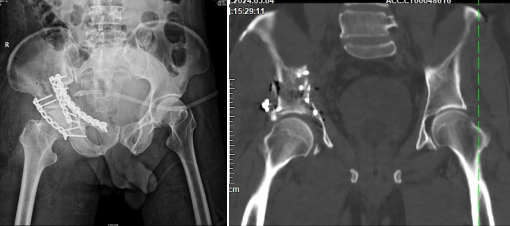

術前DR、CT重建片

為了攻克這一難題,云城區人民醫院骨科團隊與華南理工大學解剖教研室、廣州市第一人民醫院數字骨科專家丁煥文采用MDT模式會診,采用3D打印技術輔助手術。數字化醫療公司通過CT數據合成3D圖像,精確復原了患者所有碎骨塊的大小和位置。云城區人民醫院骨科團隊在體外模擬了手術復位固定過程,作出精準術前規劃,為手術的成功奠定了堅實基礎。